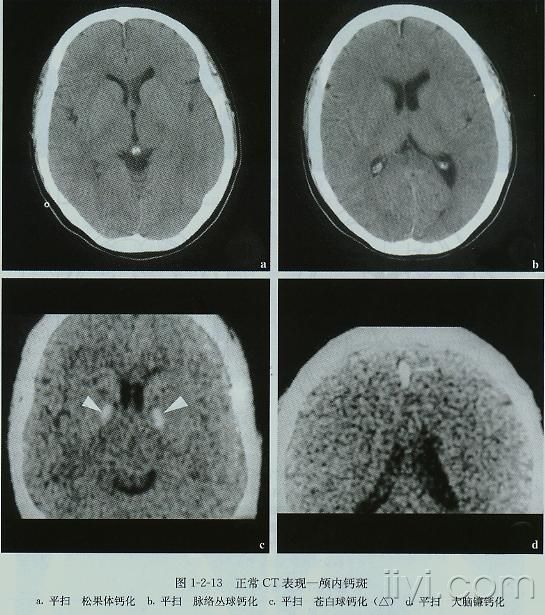

27、纵裂 (Interhemispheric fissure) 28、内囊前肢 (Anterior limb of internal capsule) 29、内囊膝部 (Genu of internal capsule) 30、内囊后肢(Posterior limb of internal capsule) 31、侧脑室三角区及脉络丛钙化(Trigone of lateral ventricle and calcified choroid plexus) 32、侧脑室枕角(Occipital horn of lateral ventricle) 绿色部分为颞叶(Temporal Lobe),浅红色部分为额叶(Frontal Lobe),黄色部分为枕叶(Occipital Lobe),褐色部分为顶叶(Parietal Lobe)skC影像园XCTMR.com | skC影像园XCTMR.com